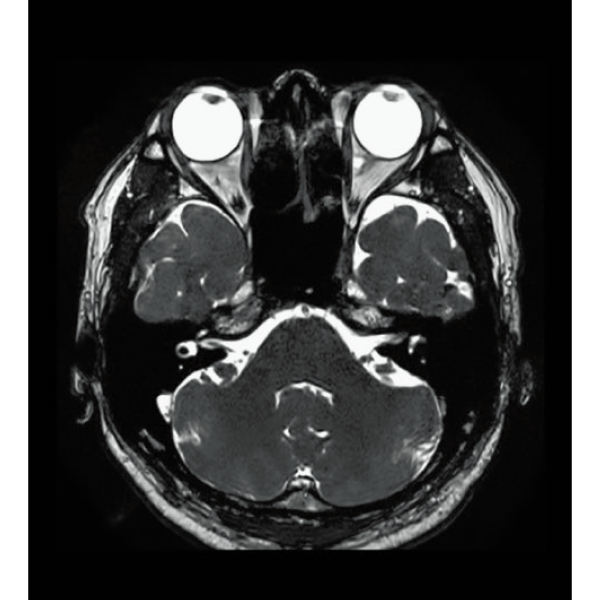

T2WI, 0.56×0.70×3.0mm, 2:28